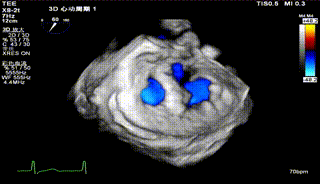

3D

怎么上穿刺鞘攻克巨大左房伴转位穿刺难关!温医大附一院周浩教授团队创新应用“导丝定位+可调弯鞘”技术完成高难度TEER手术_https://www.jmylbn.com_新闻资讯_第9张

3D带彩